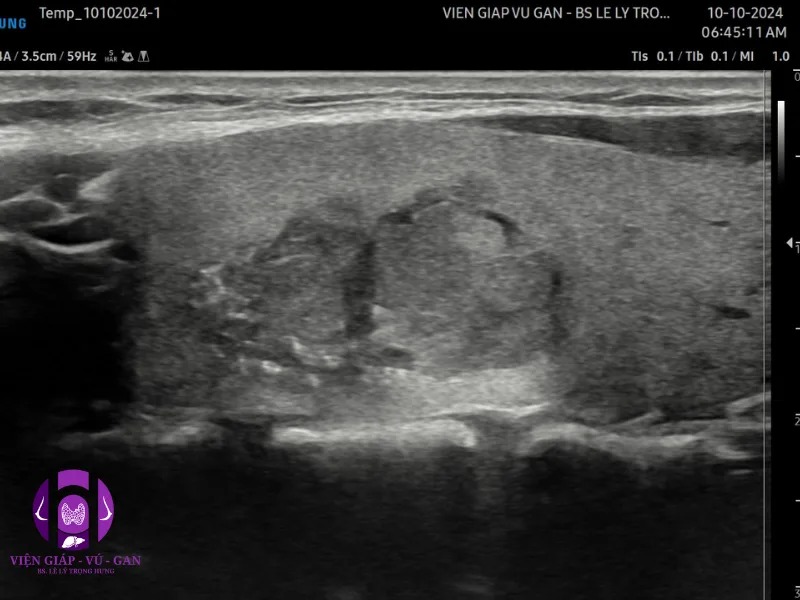

SIÊU ÂM ( Sumsung V8 ) ghi nhận :

- Tuyến giáp thùy phải: nửa trên có nhân đặc echo kém, bờ không đều, vi vôi, mạch máu phân bố ngoại vi và rải rác trung tâm kt#22x10x18mm

- Hạch cổ phải nhóm III có 1 hạch echo kém, mất rốn, hóa nang , kt #24x20mm